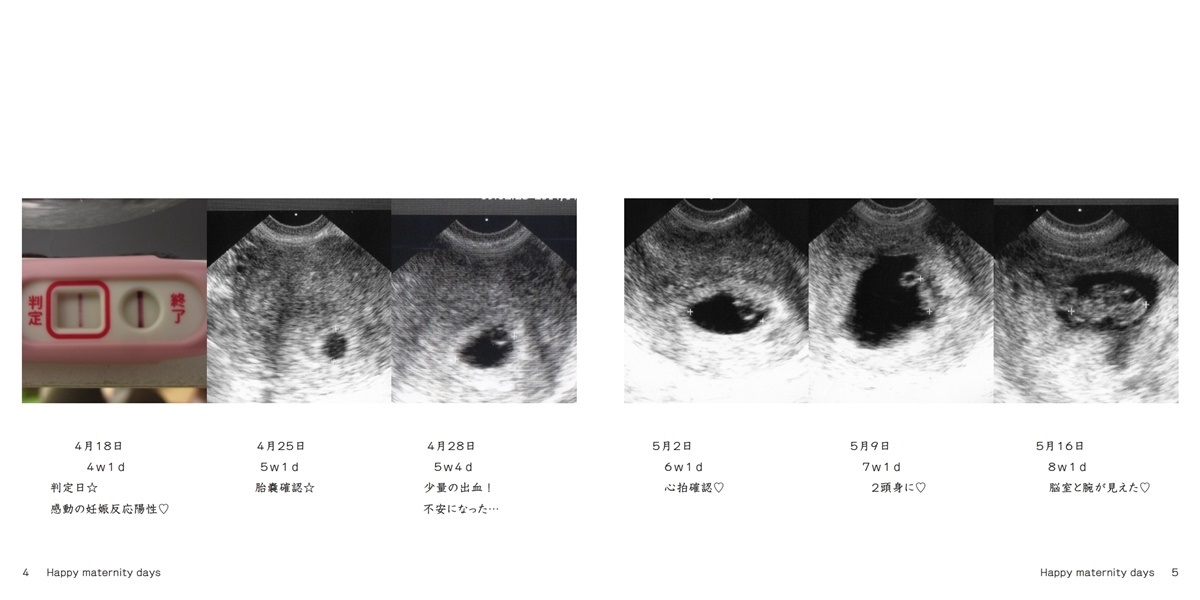

ハッピークローバーの作品 Happy Maternity Days フォトブック フォト 写真 アルバム作成ならphotoback

妊娠6w1d期待と不安が入り交じる心拍確認|妊娠初期2 投稿日: 更新日: 妊娠5週で無事に胎嚢確認ができて、次なる関門は心拍確認。BT25 6w1d 心拍確認 アヌコ37歳不妊治療 奮闘記 18年09月16日 1627 ※陽性判定後の記事です現在の病院を卒業するまでこちらのジャンルに在籍させて頂こうと思っていますこんにちはアヌコです心拍確認の日BT25 (9/15D48)6w1d・動くと息切れし怠い・胸の張りと はじめまして。 大阪出身のmeiです。 30代の管理栄養士で、保育園→クリニック→病院で勤務経験があります。 更に"食"の道を追求するため野菜ソムリエの資格を取得し、フリーランスとして新たな道を歩もうとしていた矢先に、産婦人科での検査で問題が